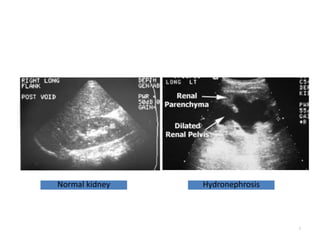

Normal kidney Hydronephrosis

Special investigations

• Ultrasound